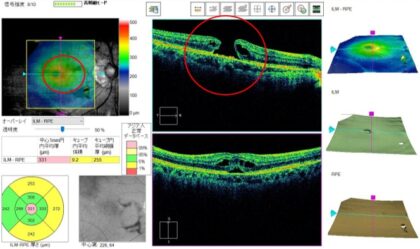

黄斑前膜(黄斑上膜)とは

- 網膜の中心部である黄斑部に薄いセロファン状の膜が生じる疾患です。

黄斑円孔とは

- 網膜の中心部である黄斑部に孔が生じる疾患です。

- はっきりとした原因は不明ですが、眼内のゼリー状の組織の硝子体と網膜の癒着が強いと、黄斑部が硝子体に引っ張られて黄斑部に孔が生じます。